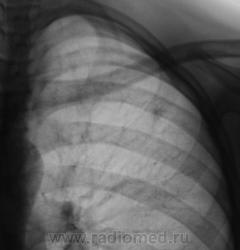

При расшифровке флюорограмм "взят на контроль". Подросток, первичная постановка на военный учёт. Жалоб нет.

Это уже не зона агрессии а конкретная тень.

Первая флюорограмма. Конечно, взяли на контроль. Разрезали. Сейчас выложу томограммы. Томограммы, как и всегда с "букетом роз".